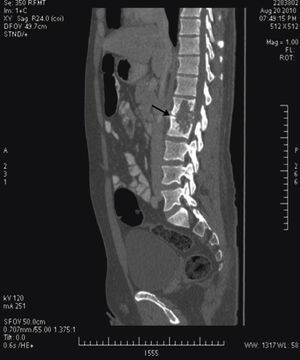

Tras el ingreso se solicitó un estudio con TC, diagnosticándose lesión lítica de borde escleroso en cuerpos vertebrales L1 y L2, centrada en el disco, compatible con espondilodiscitis. Se acompañaba de un gran absceso en el psoas y musculatura lumbar izquierda, que desplazaba hacia delante el riñón izquierdo y se extendía a tejido subcutáneo (figs. 2 y 3). La punción guiada por TC permitió retirar 440 cc de líquido purulento y aspecto caseoso. La baciloscopia de este encontró positividad con 10 bacilos/campo y el cultivo demostró crecimiento de Mycobacterium tuberculosis complex.

El interés de este caso recae en la presentación inespecífica y larvada del cuadro clínico a pesar de la afectación tan notable que se aprecia en las imágenes de la TC. Además, demuestra la utilidad de tal estudio en el diagnóstico para un tratamiento oportuno, para demostrar una afectación tan notable como la de la imagen.